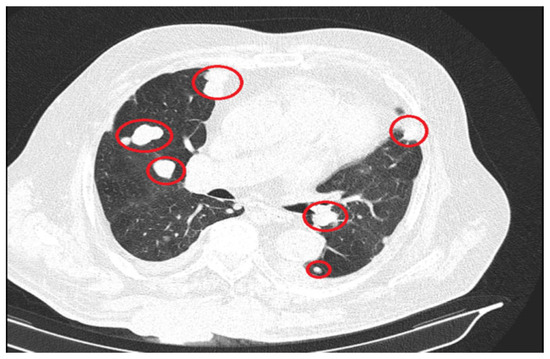

The significant progression of suggestive lesions for secondary determinations with diffuse distribution in the pulmonary parenchyma, pulmonary pleura, and mediastinal pleura were reported, along with the occurrence of pleural fluid in a small quantity bilaterally (Figure 4).

Figure 4. Secondary determinations located in both lung parenchyma.